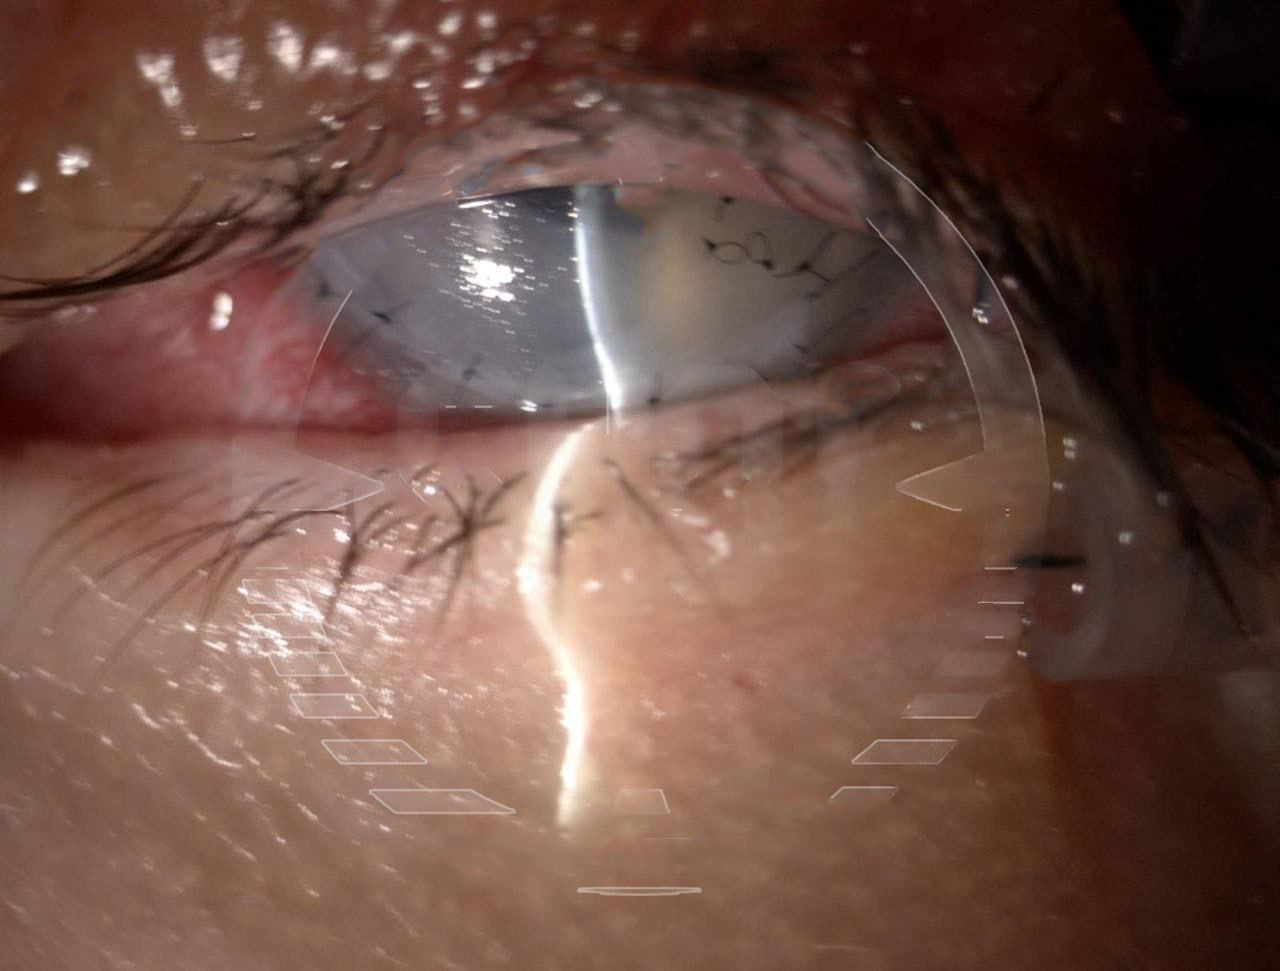

Москвичка ослепла после блефаропластики.

46-летняя жена президента Федерации еврейских общин Бороды сделала операцию по изменению формы век 23 октября, и почти сразу начались проблемы.

Женщину выписали спустя неделю в плохом состоянии: глаза не закрывались, и боль была невыносимой. Клиника прописала капли, от которых она начала слепнуть. Другой врач диагностировал отслоение роговицы, и женщине срочно потребовалась помощь в Италии. Итальянский хирург смог вернуть зрение лишь на одном глазу и всего на 30%. Впереди еще ряд операций.